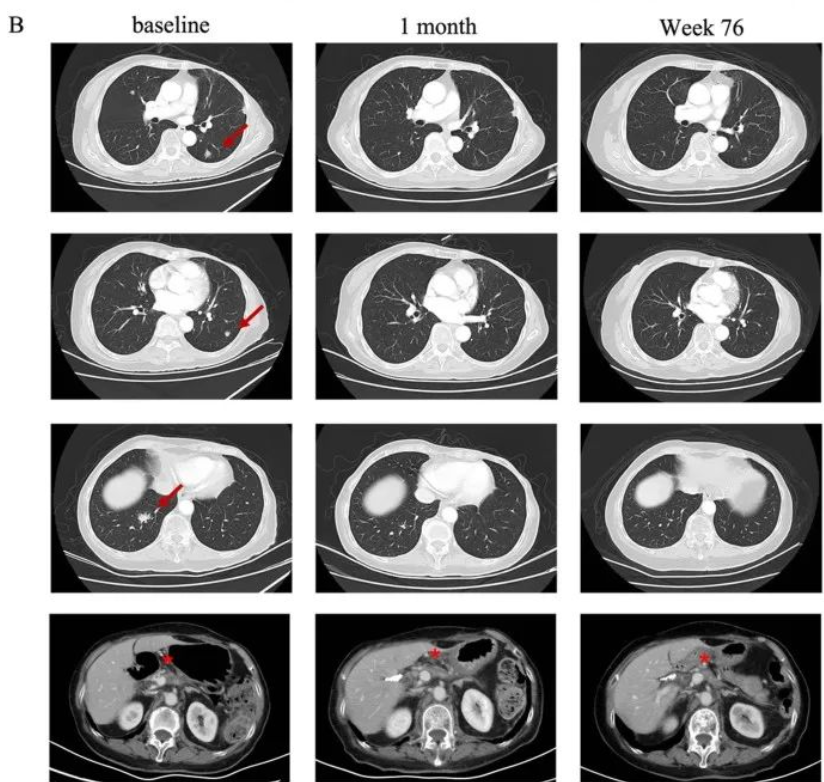

这两位幸运的患者是2015年入组时已出现下腔静脉癌栓,其中一名患者还出现腹膜后淋巴结转移,临床上已经没有更好的治疗方案,预后很差的晚期患者。让所有人喜出望外的是,2名患者在接受局部治疗和 CAR T 细胞联合治疗后的长期随访中均保持了无肿瘤状态。近日,2名患者返回医院复查,证实肿瘤完全缓解已长达7年和8年。

50岁男性肝细胞癌患者多种治疗后病情进展,并出现了下腔静脉癌栓,病情危急,接受CAR-GPC3 T细胞治疗6个月后的复查结果显示,AFP恢复正常,影像学也完全没有了肿瘤迹象。目前已无癌长达8年(2015年7月至2023年8月),回归了正常的生活。

54岁男性肝细胞癌术后3个月复发,多次治疗后下腔静脉癌栓和腹膜后淋巴结转移,临床上已无更好的治疗方案,入组了在中国进行的CAR-GPC3 T细胞临床试验,仅2周,达到了完全缓解,目前已实现7年以上无瘤生存(2016 年7月至2023 年 8 月)。

并且在长达7-8年的时间里,两名患者仅接受口服抗乙型肝炎病毒药物治疗,未接受其他癌症治疗。